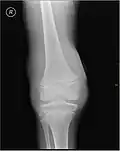

Près d'un quart des lésions sévères des ligaments et des genoux capsulaires entraînant une hémarthrose sont associées à des lésions cartilagineuses pouvant mener à une arthrite dégénérative progressive.

Radiographie montrant un début d'hémarthrose.

Radiographie montrant les complications liées à l'hémarthrose.